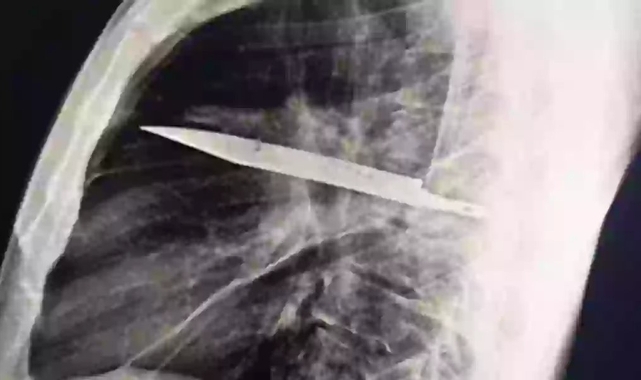

Hasta, “göğüs ağrısı” şikayetiyle değil; sağ memesinin altından fekal (irinli) bir akıntı gelmesi üzerine hastaneye gitti. Önemli diğer semptomlar—nefes darlığı, öksürük, ateş gibi—gözlemlenmedi. Genel sağlık durumu normaldi .Ayrıntılı sorgulamada, sekiz yıl önce yaşadığı bir kavga sırasında yüzüne, sırtına, göğsüne ve karın bölgesine birçok bıçak darbesi aldığı ortaya çıktı. Bu olay sonrası sadece yüzeysel bir pansuman uygulanmış, görülen hastanede röntgen veya görüntüleme yapılmamıştı .Yıllarca herhangi bir belirti yaşamayan adam, tekrar başvurduğunda yapılan röntgen görüntüsünde, sağ kürek kemiği (skapula) hizasından göğsüne saplı halde bir bıçak parçası tespit edildi. Bıçak, çevresinde nekrotik doku ve iltihap birikimiyle çevrilidir .Müdahale ve SonrasıHemen cerrahi müdahale gerçekleştirildi; bıçak cerrahi olarak çıkarıldı ve enfekte doku temizlendi. Operasyonu takiben hasta yoğun bakımda izlendikten sonra yaklaşık 10 gün içinde taburcu edildi. Takip muayeneleri sorunsuz geçti ve hastanın durumu iyiydi .